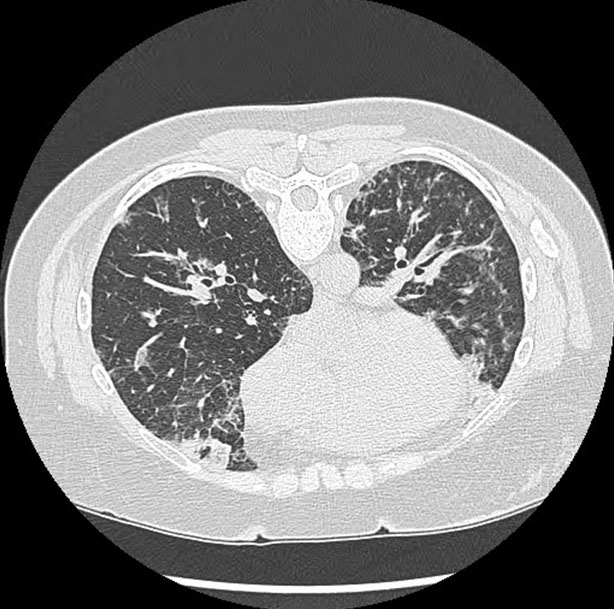

In this case, the patient’s continued progression through the three phases of EGPA forced the physicians to adapt their treatment plan as the diagnosis developed. The asthma stage persisted for around 20 years and the accompanying symptoms were treated as needed with rescue and long-term inhalers. Throughout the 20 years, periodic lung infiltrates also occurred, and antibiotics and steroids were given to fight a presumed bacterial pneumonia. During these treatments, the steroids more likely had a larger effect than the antibiotics as the pulmonary infiltrates may have been caused by the persistent peripheral blood eosinophilia that can occur during the asthmatic phase of EGPA [25]. It was not until two days before the presentation of this case when the extremely elevated blood eosinophil count (81%) and pulmonary infiltrates turned the pulmonologist’s and eventually the hospitalist’s attention to treating eosinophilic pneumonitis. At this point, 40 mg methylprednisolone sodium intravenous twice daily was administered in the hospital, and the patient’s eosinophilia returned to normal limits (0%). The patient was discharged and told to continue 40 mg of prednisone daily. Follow-up appointments with the pulmonologist and a CT chest without contrast (Figure 3) two months after the presentation showed complete resolution of symptoms and of the previously identified areas of consolidation and ground-glass opacities throughout the lungs with no residual infiltrates or pleural effusions. Pulmonology started patient on a taper dose of 30 mg prednisone daily until the next visit, along with a referral to the rheumatologist for further investigation of the persistent positive ANA titer of 91 and positive SSA antibody with no peripheral signs of rheumatoid arthritis or Sjögren’s syndrome. The rheumatologist repeated an ANCA screen which came back with a new positive c-ANCA, the last diagnostic criteria needed to diagnosis EGPA. The rheumatologist recommended the patient continue 10 mg prednisone daily and start on 100 mg azathioprine tablet daily, which the patient tolerated with no medication side effects. Additionally, the patient had no significant ongoing wheezing or shortness of breath while using her rescue bronchodilator less than twice a week.

Figure 3: Computed tomography (CT) of the chest without contrast post-admission—complete resolution of previously identified areas of consolidation and ground-glass opacities throughout the lungs with no residual infiltrates or pleural effusions.